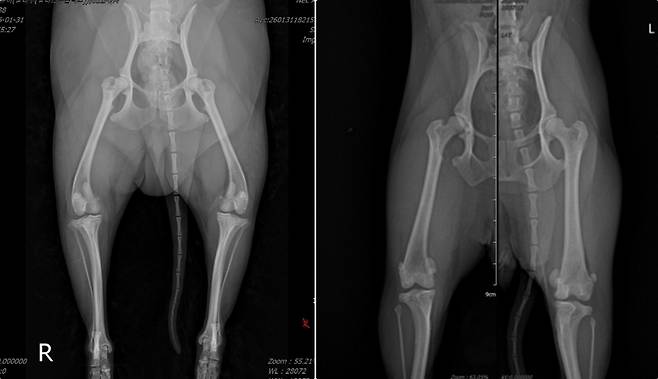

23일 넬동물의료센터 내 정형외과 동물병원 바르고바르개에 따르면 정형외과 수술의 출발점은 정확한 방사선(X-ray) 촬영이다. 방사선 사진은 수술 계획의 설계도 역할을 한다. 촬영 자세가 조금만 틀어져도 뼈 정렬과 변형 정도를 잘못 판단할 수 있다.

이 원장은 "정확한 방사선 촬영과 이를 구현하는 수술 경험이 치료 결과를 좌우하는 핵심 요소"라고 설명했다.